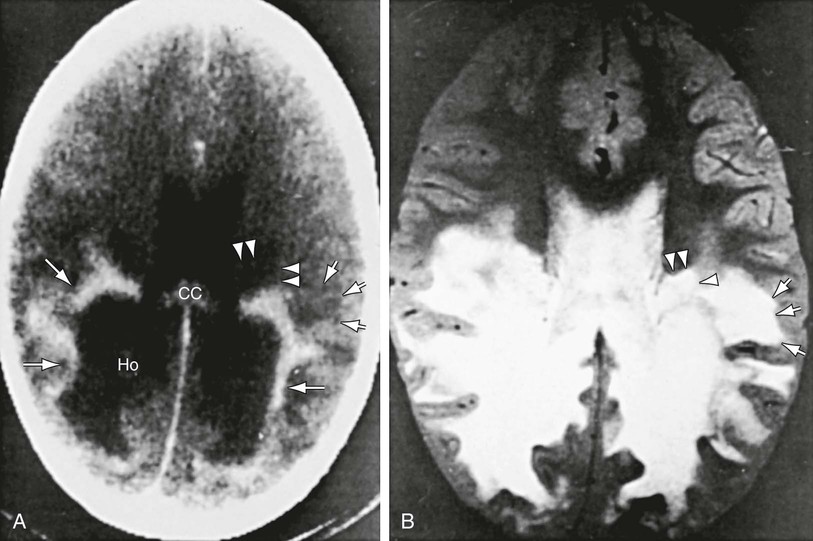

Patients with childhood cerebral or adolescent ALD show cerebral white matter lesions that are characteristic with respect to location and attenuation patterns on MRI. In 80% of patients, the lesions are symmetric and involve the periventricular white matter in the posterior parietal and occipital lobes. Approximately 50% show a garland of accumulated contrast material adjacent and anterior to the posterior hypodense lesions (Fig. 86-5A). This zone corresponds to the zones of intense perivascular lymphocytic infiltration where the blood–brain barrier breaks down. In 12% of patients, the initial lesions are frontal. Unilateral lesions that produce a mass effect suggestive of a brain tumor may occur. MRI provides a clearer delineation of normal and abnormal white matter than does CT (Fig. 86-5B).